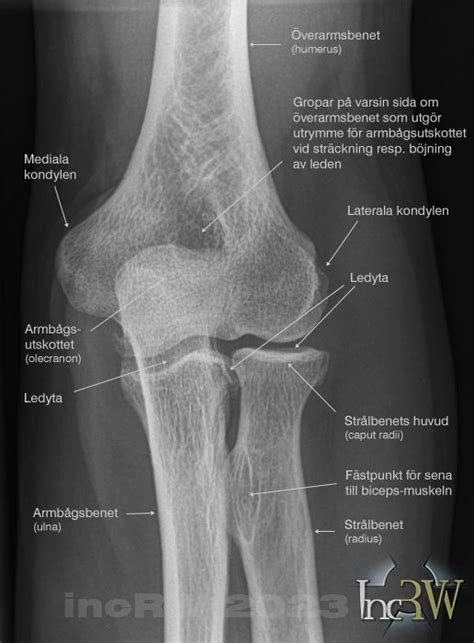

Art. humeri, axelleden, är den stora leden i skuldergördeln. Det är en av kroppens rörligaste leder, detta främst på grund av ledens utformning. Det är en kulled som ligger mellan ledhuvudet caput humeri och ledpannan cavitas glenoidalis. Här är några tips och råd som kan hjälpa dig att få större och starkare armar:. Pronator teres.

Över och under ledpannan finns två tuberkler (tuberculum infraglenoidale och tuberculum supraglenoidale); m. biceps brachiis sena fäster i den övre. Axelleden omges av bursor (slemsäckar) som minskar friktionen: b. subacromialis, b. subcoracoideus, b. musculus subscapularis och b. subdeltoidea. Här är några populära bicepsövningar som kan hjälpa dig att nå dina mål:. Symphysis pubica — Blygdbensfog.